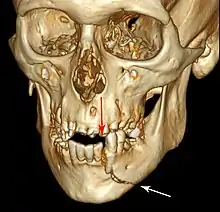

![]() | |

| 3D computed tomographic image of a mandible fracture in two places. One is a displaced right angle fracture and the other is a left parasymphyseal fracture. | |

3D CT reconstruction of mandible fracture, white arrow marks fracture, red arrow marks moderate displacement and open bite